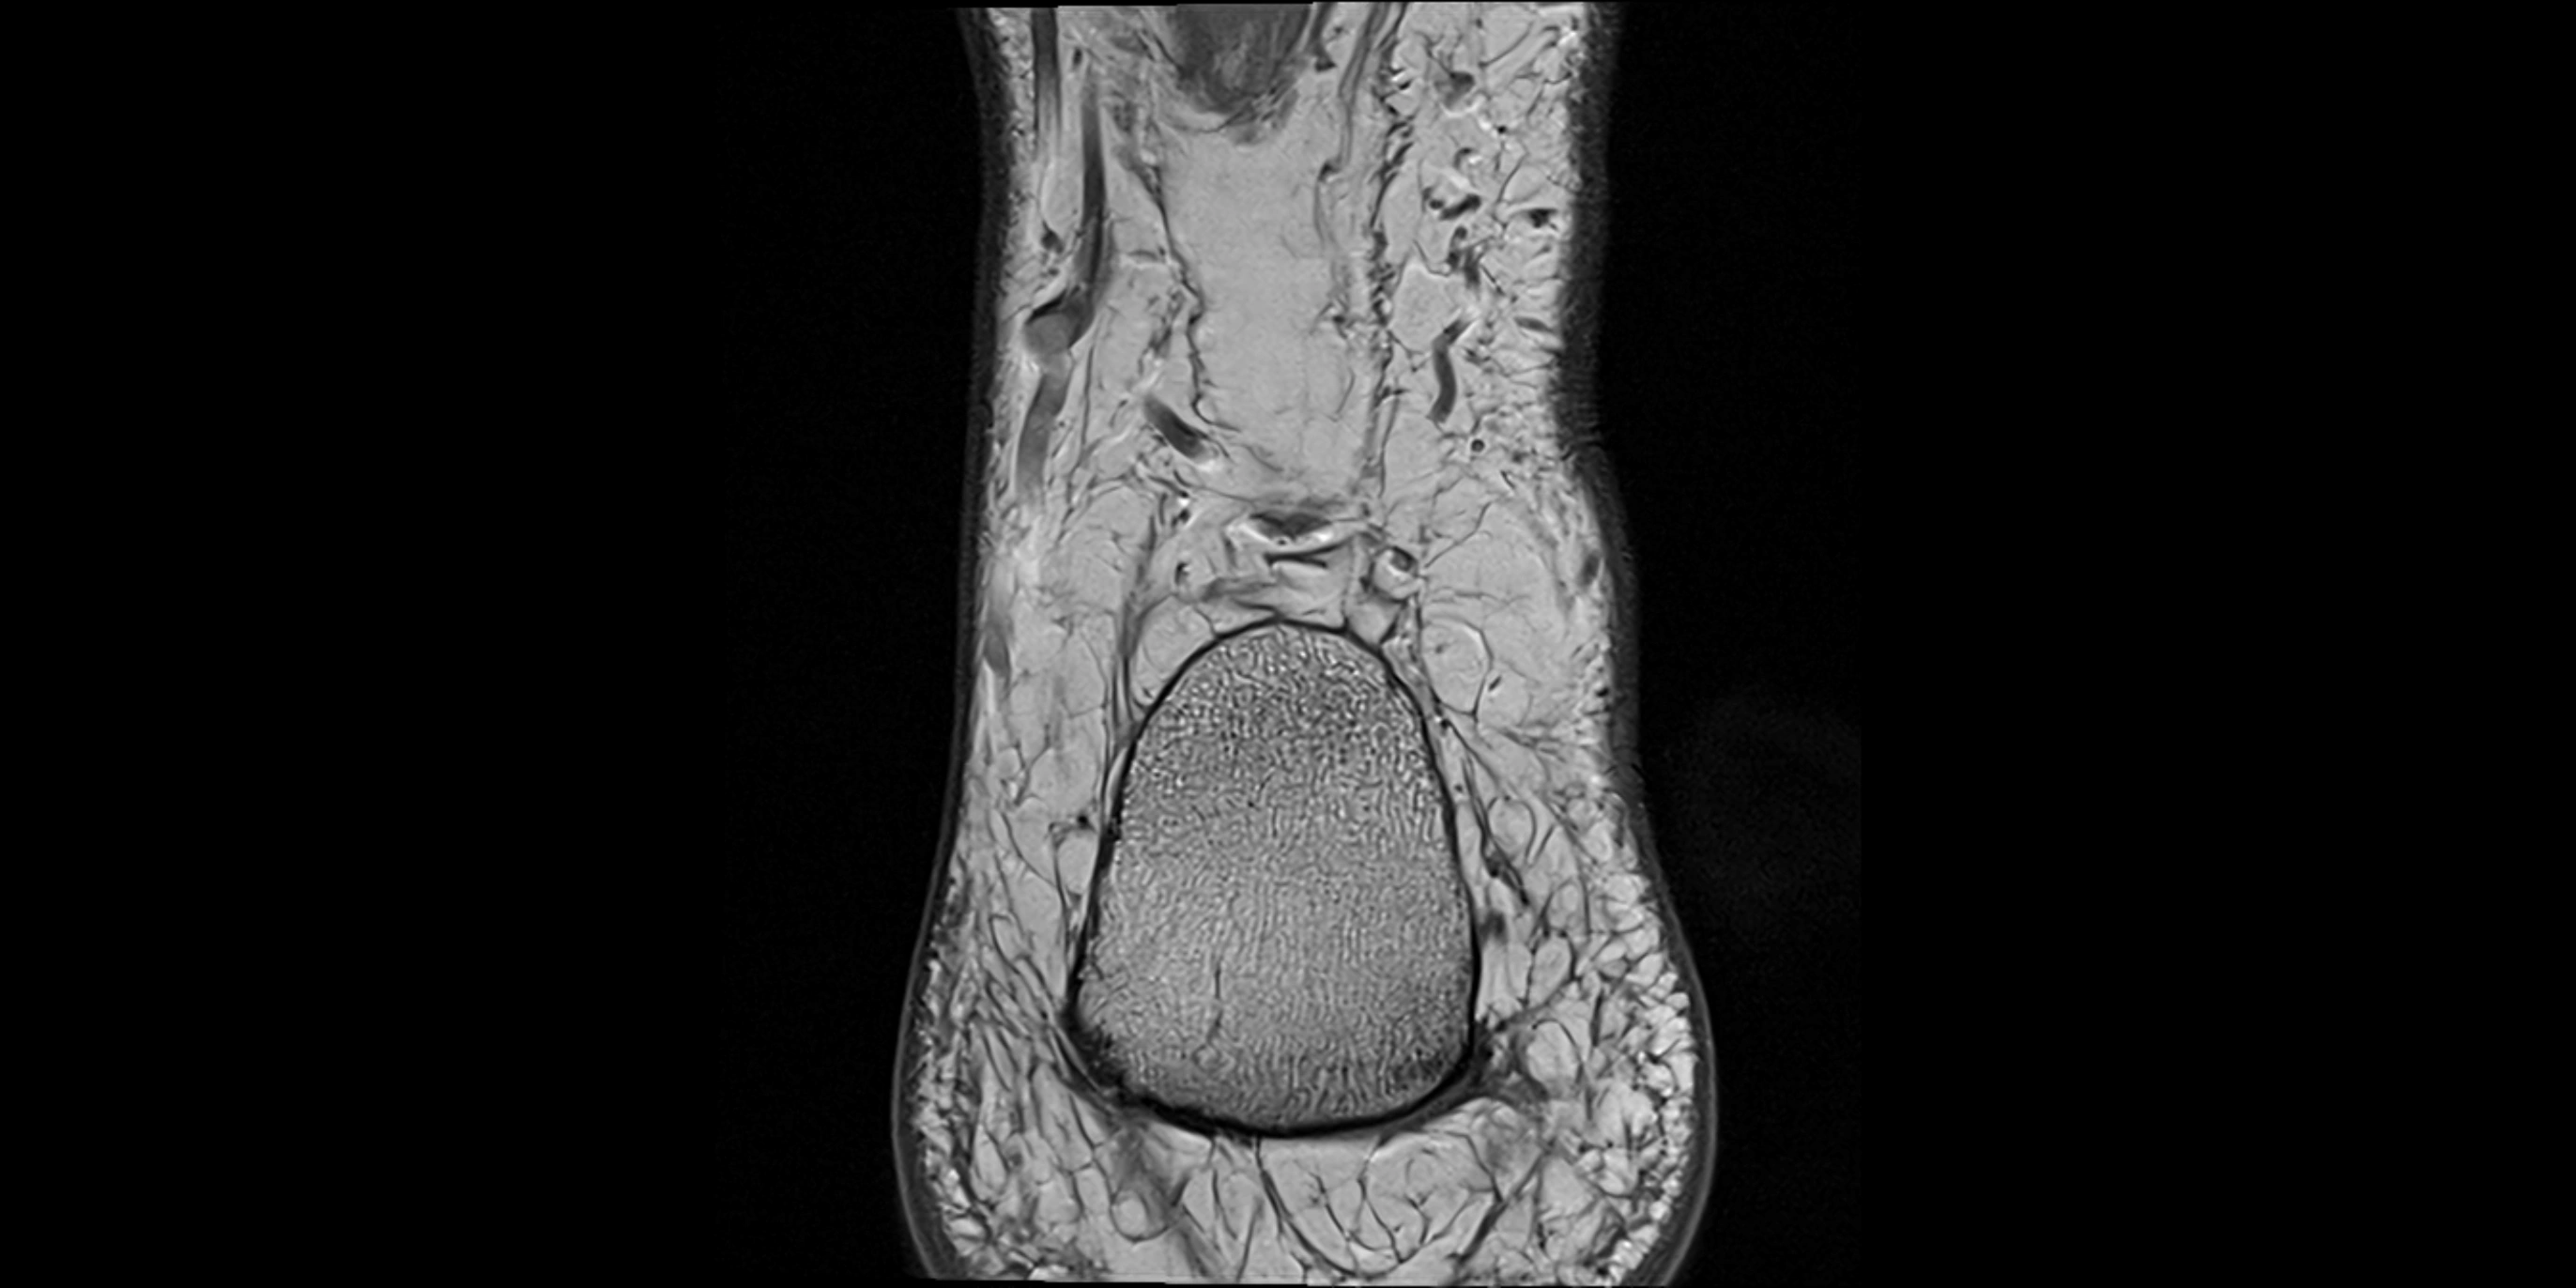

MRI image

image